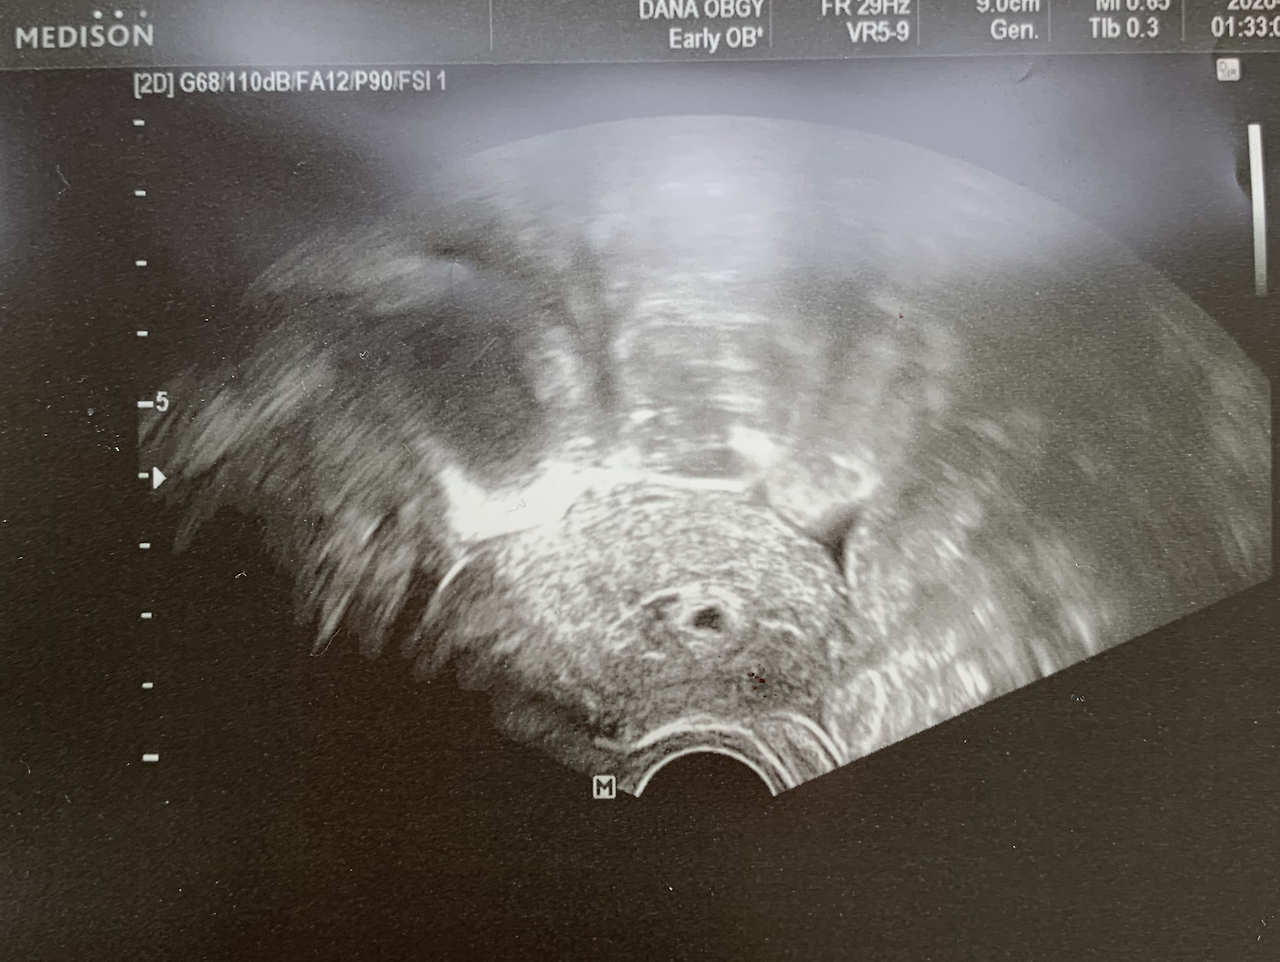

점처럼 생겨난 아기집! 첫 초음파 사진 :)

임신 4주 차. 기쁨이가 우리한테 왔다!